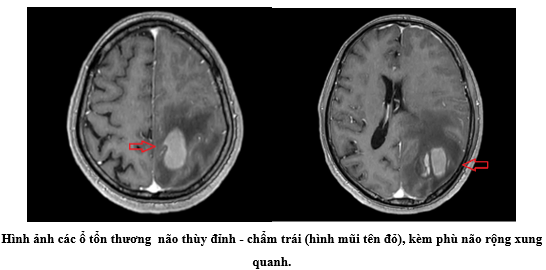

- Cộng hưởng từ sọ não: Nhu mô não thùy đỉnh - chẩm trái có các ổ tổn thương tín hiệu không đều, có phần hạn chế khuếch tán, ngấm thuốc sau tiêm, phù não rộng xung quanh, gây hiệu ứng khối đè ép não thất bên bên trái, đẩy đường giữa sang phải 7mm, có ổ ở thùy chẩm trái chảy máu giảm trên T2*, ổ lớn nhất ở thùy đỉnh trái kích thước 32x20mm.

Hình ảnh cộng hưởng từ sọ não cho thấy nhiều ổ tổn thương thùy đỉnh – chẩm trái, ngấm thuốc mạnh sau tiêm, kèm phù não rộng và hiệu ứng khối rõ rệt, có đẩy lệch đường giữa và ổ xuất huyết trong tổn thương. Đây là những đặc điểm hình ảnh thường gặp của di căn não. Sự hiện diện của xuất huyết trong ổ di căn càng củng cố khả năng nguồn gốc từ ung thư tuyến giáp, melanoma hoặc ung thư thận, trong đó ung thư tuyến giáp thể nhú cần được cân nhắc ngay cả khi tổn thương nguyên phát không rõ ràng.